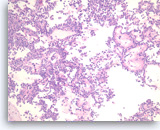

Small cell carcinoma,

Pancreas FNA, Cell Block.

The tumor cells with high nuclear to cytoplasmic ratios are present singly and in loose groups. Necrosis is present.

20X